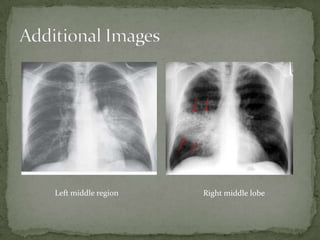

A 76-year-old female presented with worsening dyspnea, cough producing yellow sputum, subjective fevers and chills, weakness and decreased appetite. Her vital signs and physical exam showed signs of infection. Chest x-rays revealed consolidation in the right middle lobe, suggesting lobar pneumonia. She was treated with oxygen, IV fluids, antibiotics and admitted to the hospital based on her condition.